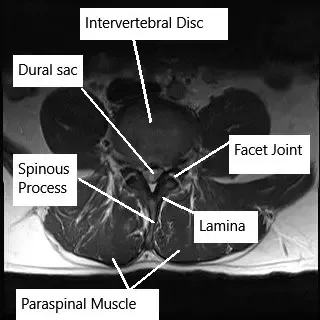

How the Body Part Normally Works? (Relevant Anatomy)

The lumbar spine consists of five vertebrae (L1-L5) separated by intervertebral discs. These discs act as shock absorbers and allow for flexibility and movement of the spine. The spinal cord runs through the spinal canal, and nerves branch out through openings between the vertebrae. These spinal nerves control the sensation and movement of the lower body, including the legs, feet, and pelvic organs. When a disc herniates, it can compress these nerves, leading to symptoms such as pain, numbness, and weakness.